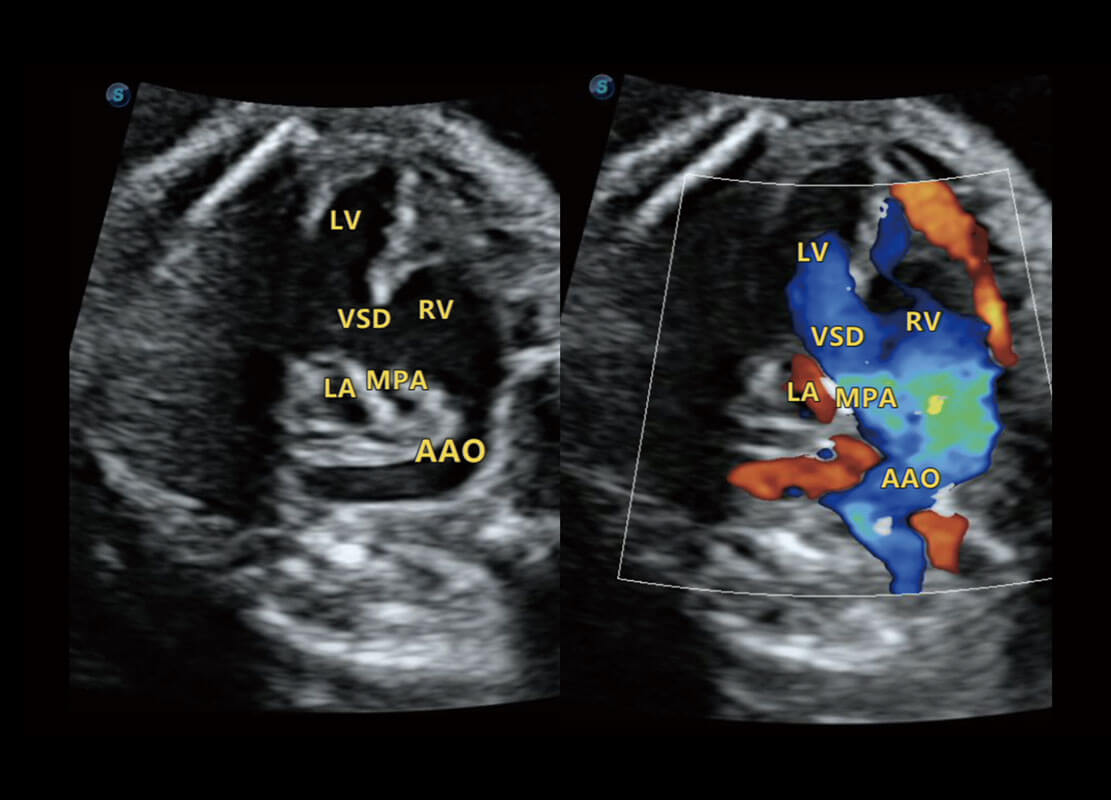

P60搭载一系列胎儿心脏成像技术,实现精细的胎儿心脏评估。

四腔切面

四腔心血流

右室双出口

胎心容积成像